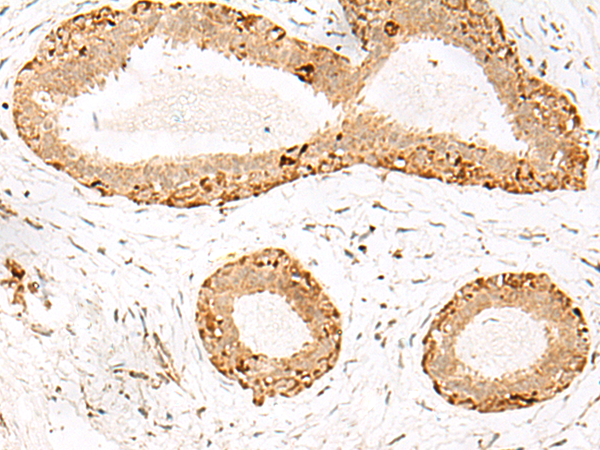

分类: 科研抗体货号: P00209别名:应用: IHC反应种属: Human, Mouse, Rat